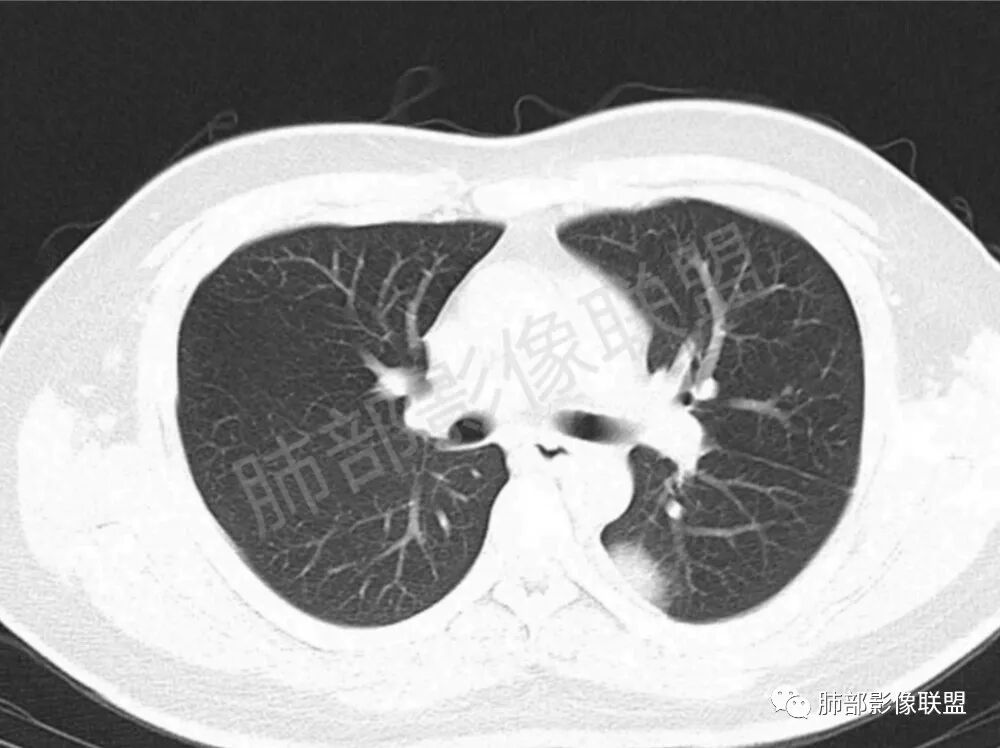

男性,22岁,HIV病史,症状半年,双肺多发大小不等结节影,边缘光滑,密度均匀,以胸膜下分布为主,部分与胸膜相连,胸膜下脂肪间隙可见,病灶近段支气管走行病灶内,远端似有堵塞,无增强图像,考虑隐球菌,鉴别:淋巴瘤,GPA

双肺多发结节影,膨隆,边缘光滑,圆顿,沿支气管血管束分布为主,部分贴胸膜,部分见空洞,空气支气管征

两肺多发结节性,大部分位于胸膜下,部分结节周围可见晕征。局部结节内可见扩张的支气管,纵隔淋巴结大,脾大,22岁男,HIV阳性,常规先考虑隐球菌。鉴别淋巴瘤,结核,马儿。

男,22,半年前咳嗽伴少痰,查HIV阳性,痰查TB阳性,既往有肺部斑片影伴空洞、纵隔淋巴结肿大、脾大。SCC、CA50、CA199、FER增高,此次胸部CT:两肺多发结节影,部分沿血管束分布,部分贴胸膜下,大小不一,密度不一,部分较散、边缘模糊,部分较实、圆钝、周围模糊晕,部分结节有支气管进入穿行自然,部分结节有血管分支自如通过。考虑HI∨相关淋巴增殖类病变,淋巴瘤?LYG?鉴别PC、TB。

青年男性,半年前咳嗽,HIV阳性,结核DNA阳性,肿标糖类抗原和铁蛋白增高。外院影像有纵隔淋巴结增大伴脾大,肺部病灶空洞。现在影像:肺内多发沿支气管分布(有支气管充气征,长轴沿支气管分布)及胸膜下分布(平行于胸膜)的大小不等结节,个别伴有空洞,双侧腋窝淋巴结肿大。纵隔图片不够,是否还有淋巴结肿大未知,脾脏未显示。

1.双肺多发大小不一结节,外围为主,边界尚清,部分周围似有GGO

2.类圆形,部分与胸膜相连,糊墙

3.支气管通畅或近端堵塞

空洞  游走  多变  支气管血管束分布,好符合啊

支气管血管束和小叶间隔分布,其实也就是沿淋巴间质分布,这个好理解

影像学缺乏特征性,以支气管血管周围、胸膜下及双肺下叶周边多发结节影最多见,结节易坏死形成空洞,伴有游走性和多变性的特征,结节周围可有磨玻璃样晕征,有时也可见单发结节影、薄壁的囊状阴影或弥漫性浸润影。肺门、纵隔淋巴结肿大少见, 可见胸腔积液和气胸。

CT表现分为四种类型∶

类肺炎型∶表现为两肺大片状密度增高影,多位于两肺下野,边缘模糊,病灶内可见支气管气相;

肿块型∶表现为两肺多发大小不等的不规则肿块,肿块边缘不光整、欠锐利,有大的分叶,毛刺少见,增强扫描呈明显强化,可合并坏死、空洞;

结节型∶表现为两肺多发大小不等的结节,以两肺中下野多见,结节边缘欠锐利;

混合型∶表现为两肺大片状密度增高影及不规则肿块或结节影。